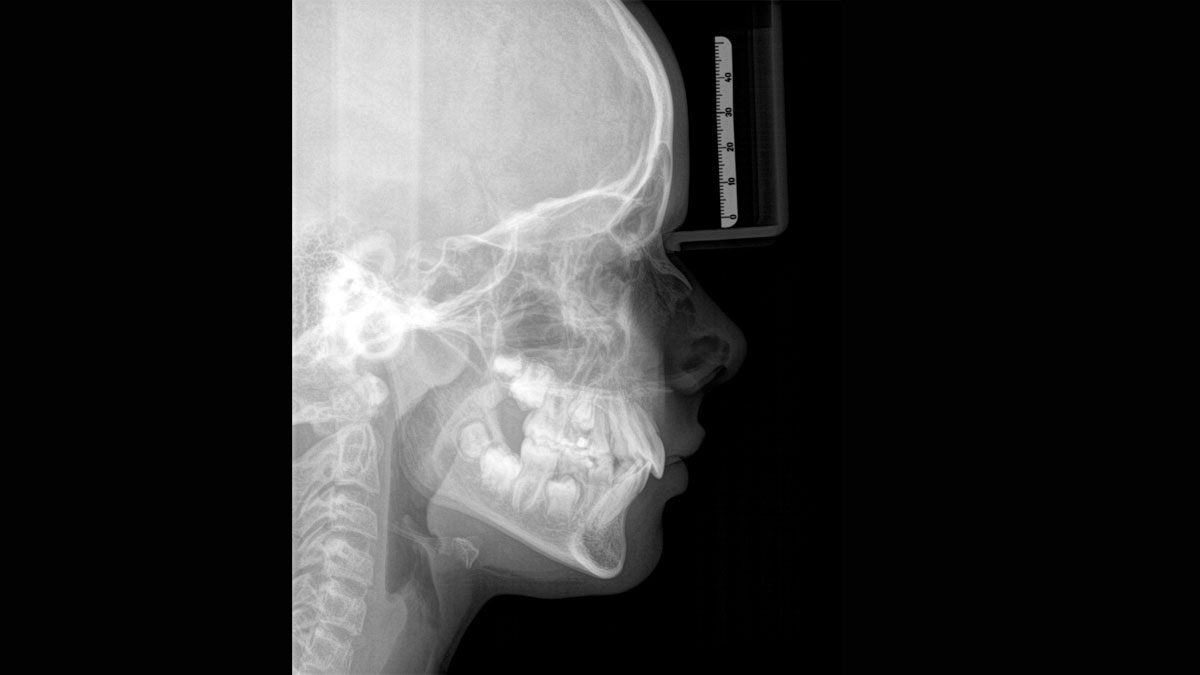

We developed a 10-point concept for easy patient positioning and X-ray imaging. Our concept is primarily about two things: high image quality and comfort for the patient and the assistant. This concept supports and provides the tools needed to ensure high-quality images for treatment analysis and focuses on ergonomics and comfort for the patient and assistant.

The patented bite block technology, for example, automatically establishes the correct inclination of the patient's head, positioning the patient in the occlusal plane, partnering with the 3 point head fixation and firm handles to ensure stable positioning-limiting unnecessary correction scans.